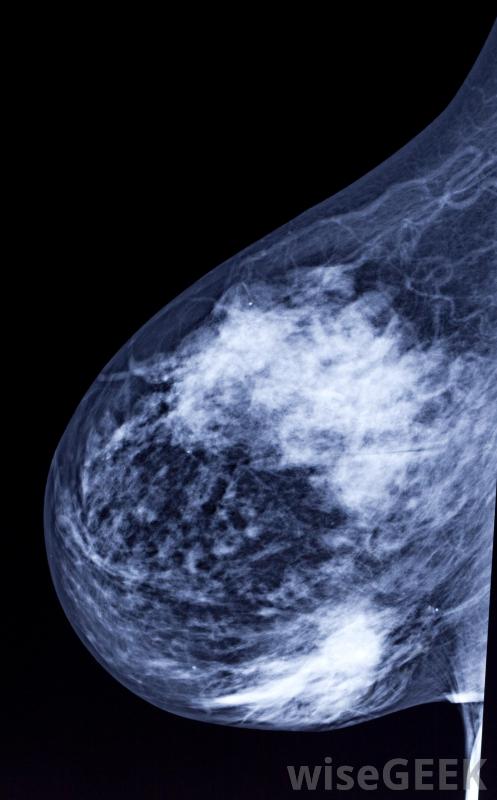

数字乳房x光摄影使用传统的x射线方法,但是乳房组织的图像是用电子x光机拍摄的,它以数字格式存储图像。图像在计算机屏幕上显示,然后放射科医生可以调整对比度,增强或放大x光片以显示检测结果。传统的乳房x光片在胶片上生...

由于胶片曝光不足或曝光过多,数字乳房X光片不再需要重复扫描。数字乳房X光片需要更少的时间来记录图像,以检查是否存在异常乳房组织,从而减少与手术相关的疼痛。检查要求将乳房放在一个平坦的表面上,在进行x光检查时,有一个装置压迫乳房。乳房的组织需要展开,以允许机器观察所有的组织,并防止组织堵塞异常在拍摄图像时,女性必须保持非常安静,避免呼吸,以防止x射线散射或无法读取的扫描乳房组织很少有研究证实数字乳房X光摄影的好处,但是一些科学家和医生已经展示了使用这项技术的有希望的结果,由于在乳腺组织成像过程中由于运动而导致扫描不可读,重复的乳房X光片减少了。数字乳房X光片允许放射科医生通过编辑技术改进测试图像,从而产生更清晰的结果,更容易检测肿块或肿瘤样结构。这种技术由于胶片曝光不足或曝光过多,也不再需要重复扫描。对于一些办公室和患者来说,测试成本是一个问题,但由于数字乳房X光片是数字化存储的,它降低了员工和存储空间的开销胶片。数字化筛查的完成速度要快得多,让放射科医生可以在一天内完成更多的乳房X光片检查。在较短的手术过程中,女性受到的辐射较少,这可能有助于缓解一些患者的安全顾虑。数字成像技术的进步可能会给筛查中心带来未来的好处,并且为病人提供更准确的结果。建议50岁以上的妇女每两年进行一次乳房X光检查。乳房X光检查可以发现可能是乳腺癌征兆的肿瘤或肿块。定期检查建议医生将之前的扫描结果与当前图像进行比较,以确定是否有变化或增长。